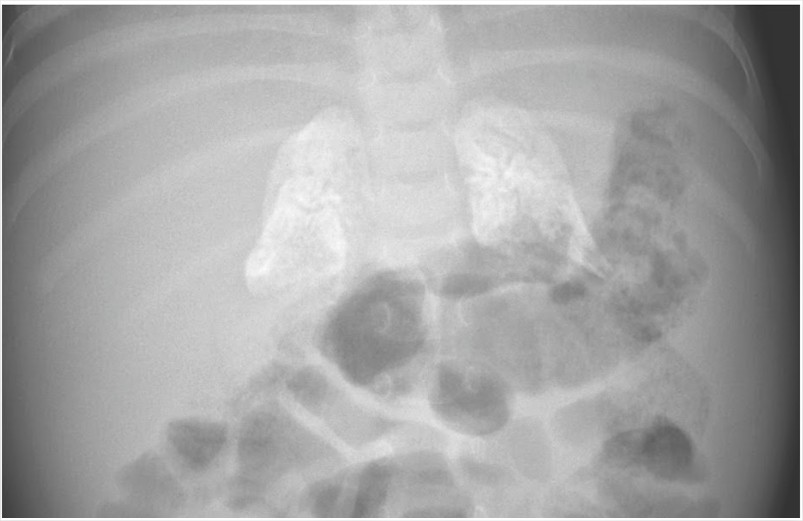

Se trata de una niña de 4 meses que fue ingresada al hospital por no presentar un buen desarrollo. El parto fue normal y sin complicaciones, tenía un peso al nacer de 3350gr y a los 4 meses presentaba un peso de 4090gr. El paciente fue alimentada con una formula a base de leche de vaca, durante la adminisón no presentaba diarrea o vómitos, la diarrea se desarrolló a los pocos días de la admisión. Los padres tenían otras dos hijas, y ambas estaban sanas. El examen físico del bebé reveló un abdomen protuberante con un hígado y bazo agrandados. Los análisis de sangre mostraron anemia normocítica, niveles elevados de aminotransferasas hepáticas e hiperlipidemia. La radiografía simple del abdomen reveló calcificación de ambas glándulas suprarrenales. Se realizó una prueba de punto seco en sangre para determinar la actividad de la enzima e indicó la deficiencia de lipasa ácida lisosomal. Se identificó una mutación homocigótica en LIPA en la secuenciación de genes, que confirmó el diagnóstico de deficiencia de lipasa ácida lisosomal, o enfermedad de Wolman, una condición metabólica autosómica recesiva. Debido a que la lipasa ácida lisosomal es crítica para el metabolismo de ésteres de colesterilo y triglicéridos, una deficiencia conduce a la acumulación de lípidos en el hígado, el bazo y el intestino, lo que causa malabsorción e insuficiencia de crecimiento, y a la calcificación de las glándulas suprarrenales. Se proporcionó asesoramiento genético y el niño fue tratado con lipasa ácida lisosómica humana recombinante. Se proporcionó una fórmula baja en grasa y nutrición parenteral. El crecimiento del paciente comenzó a mejorar, y a los 9 meses de edad pesaba 6500 g (puntaje z, 2,6). Su desarrollo está mejorando constantemente, pero la demora psicomotora aún está presente.